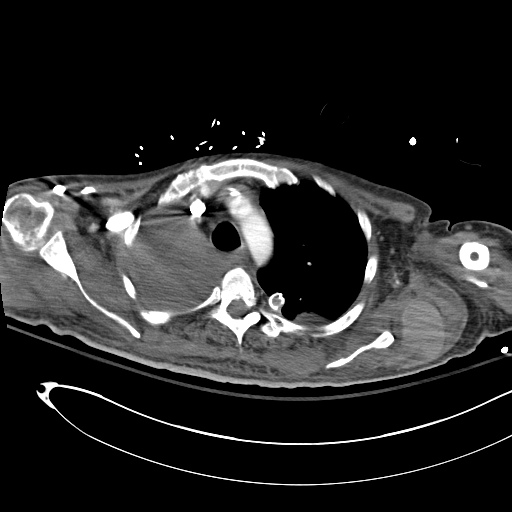

Chest Medicine Made EasyDr Deepu Black Pleura Sign Pleural Tag Sign Radiology Pleural tags refer to slender bridges of soft tissue seen on ct scans that extend between masses in the lungs and the pleura. By univariate analysis and multivariable adjustment, surgical history, tumour marker (tm), number of pleural tags, length of solid contact and obstructive inflammation were identified as independent risk predictors of pleural invasiveness (p= 0.014, 0.003, <0.001, <0.001, and. Pleural Tag Sign Radiology.

Snippet The Jellyfish and Multiple Pleural Tag Signs Pleural Tag Sign Radiology Pleural tags refer to slender bridges of soft tissue seen on ct scans that extend between masses in the lungs and the pleura. Intrapulmonary lymph nodes are typically. Department of radiology, concord repatriation general hospital, concord, new south wales, australia. Juxtapleural lung nodules can be defined by their location within 15 mm of a pleural surface. By univariate analysis and. Pleural Tag Sign Radiology.

Radiata or Corona Maligna and Pleural Tail Sign Radiology Key Pleural Tag Sign Radiology Intrapulmonary lymph nodes are typically. Type 2 pleural tags on conventional ct images can increase the accuracy of early diagnosis of visceral pleural invasion by nsclc that does not abut the. Department of radiology, concord repatriation general hospital, concord, new south wales, australia. Juxtapleural lung nodules can be defined by their location within 15 mm of a pleural surface. By. Pleural Tag Sign Radiology.